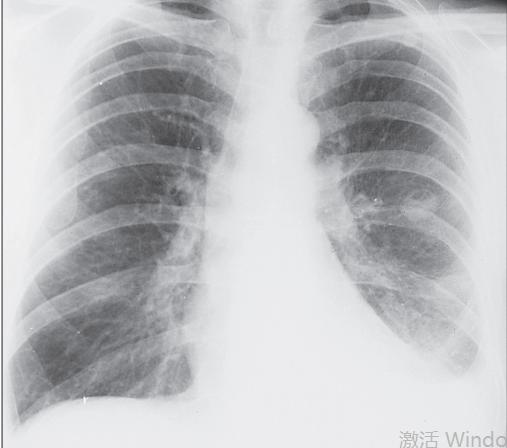

RA的胸膜病变,也可看到类风湿结节、弥漫性肺间质病变

而RA的呼吸系统损伤里最影响患者生活质量和预后的是:间质性肺疾病(interstitial lung disease, ILD)、闭塞性细支气管炎(obliterative bronchiolitis, OB)、药物反应和感染。

导致ILD的危险因素是:更严重的RA病情、抗环瓜氨酸化肽抗体(ACPA)阳性、男性、年龄较大和吸烟。最简单有效的措施是戒烟、避免二手烟。多数的RA所致的ILD发生在50岁后的病人。但症状往往是隐匿起病,最初仅仅表现为劳力性呼吸困难和干咳。由于关节病变可限制患者的运动,所以劳力性呼吸困难的发现可能延迟。虽然医生检查时可以听到双肺底爆裂音,但没有的患者不意味着没有ILD。高危患者定期行胸部HRCT、肺功能检查都是必要的。